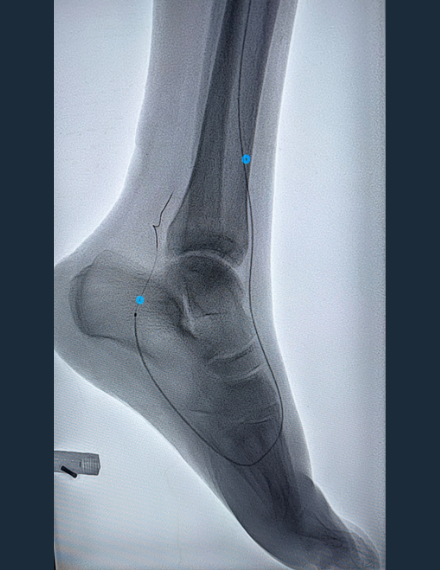

Pre-Procedure Angio

Occlusive calcium in AT extending into DP -

Pre-procedural vascular testing showed absent great-toe pressure, occlusion of the distal anterior tibial and dorsal pedal arteries, and a patent but low-velocity bypass graft with poor distal outflow consistent with chronic limb-threatening ischemia. The distal AT and DP lesions were traversed intraluminal and Shockwave Javelin was used to modify the heavily calcified plaque followed by a percutaneous transluminal angioplasty (PTA) balloon.